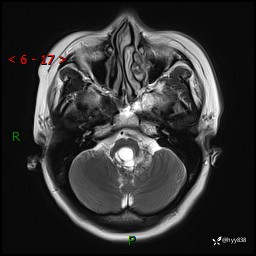

性别:女

年龄:47岁

简要病史:头晕1年余,间断恶心不伴呕吐

颅脑MRI平扫+DWI

轴内、轴外占位

病灶的影像特征

轴内或轴外肿瘤